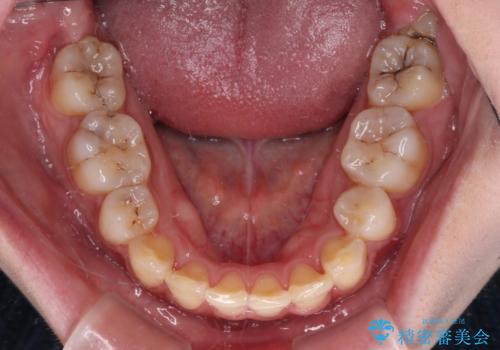

- 八重歯やデコボコをインビザラインで治療したいとのことで来院された患者様です。

インビザライン単体で治療を行うには叢生が強いと判断されたため、事前にワイヤー装置で抜歯矯正を行い、ある程度改善してからインビザラインにて仕上げていくこととしました。